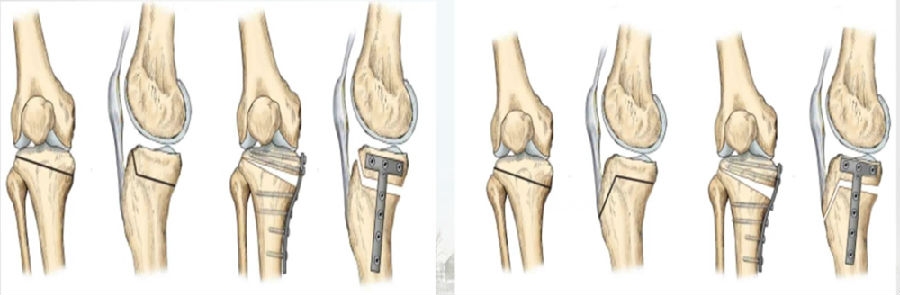

(1)OWHTO可分为上行性或下行性两种截骨方式。

(2)上行性OWHTO可降低髌骨高度的2%-11%;当髌骨高度下降10%,可引起髌股关节压力改变,引发膝前痛。

OWHTO上行截骨与下行截骨

(3)下行性OWHTO对髌骨高度影响较小。

(4)术前存在低位髌骨、髌股关节炎或内翻矫正度数较大时可考虑下行性OWHTO。

有文献证实下行截骨对髌骨的高度确实没有明显影响。

OWHTO下行截骨对髌骨的影响